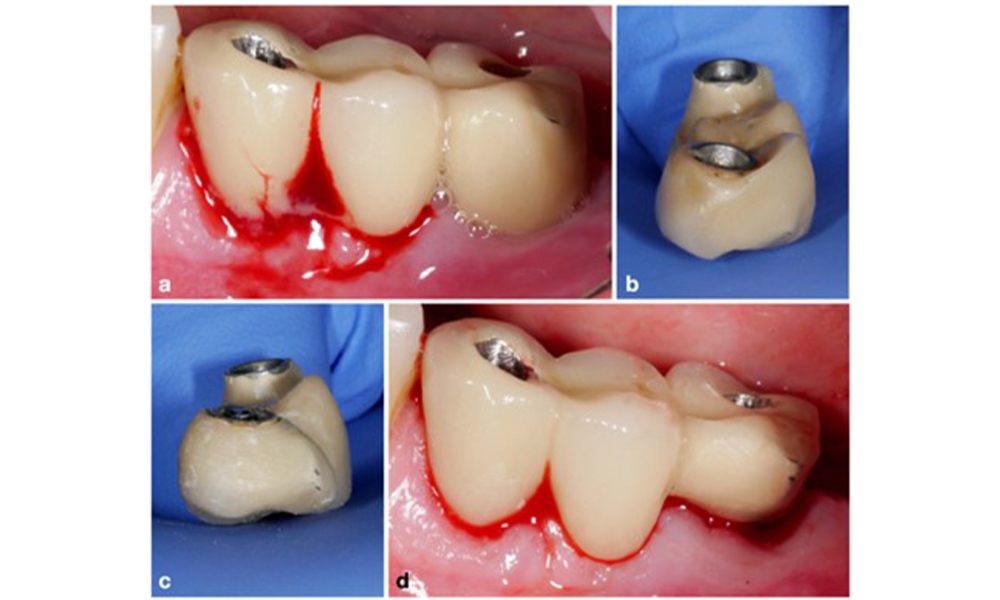

Die prothetische Restauration sollte bei einer nicht-chirurgischen ebenso wie bei einer chirurgischen Behandlung abgenommen werden, um einen besseren Zugang zur Implantatoberfläche zu ermöglichen. Die Wahl der chirurgischen Intervention (z. B. resektiv, rekonstruktiv oder eine Kombination) hängt von mehreren Faktoren ab: (1) Morphologie des Defekts (z. B. horizontal, Dehiszenz, intraossär oder eine Kombination) (Abb. 10), (2) Implantatoberfläche (also gedreht oder modifiziert/„rau“) und (3) Vorhandensein oder Fehlen einer ausreichend keratinierten und anhaftenden Schleimhaut.